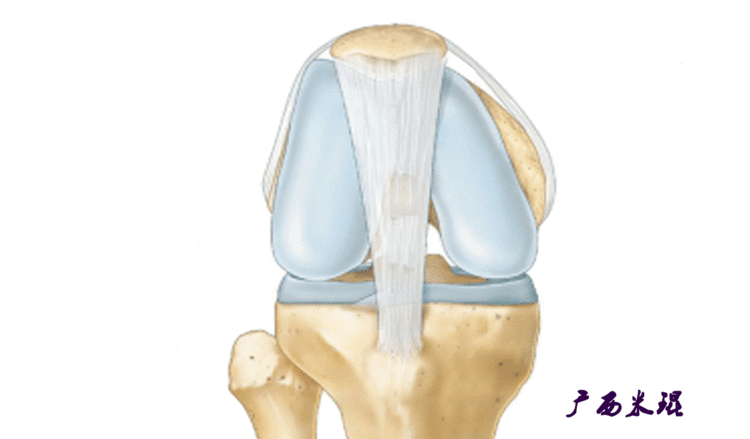

说到髌骨脱位,首先就要了解髌骨,髌骨是人体最大的籽骨,倒三角状位于膝关节前方,它的上缘与股四头肌腱相连,下缘通过髌韧带止于胫骨结节上,两侧为股四头肌扩张部,髌骨后方的凸面为光滑的关节面,与股骨下端内外髁之间的滑车凹面关节面形成关节。尽管股四头肌中的股直肌、股中间肌、股外侧肌的作用方向与髌韧带不在一条直线上,髌骨有向外突出的倾向,但因股内侧肌有向内上方牵拉作用力而使髌骨维持在正常位置。